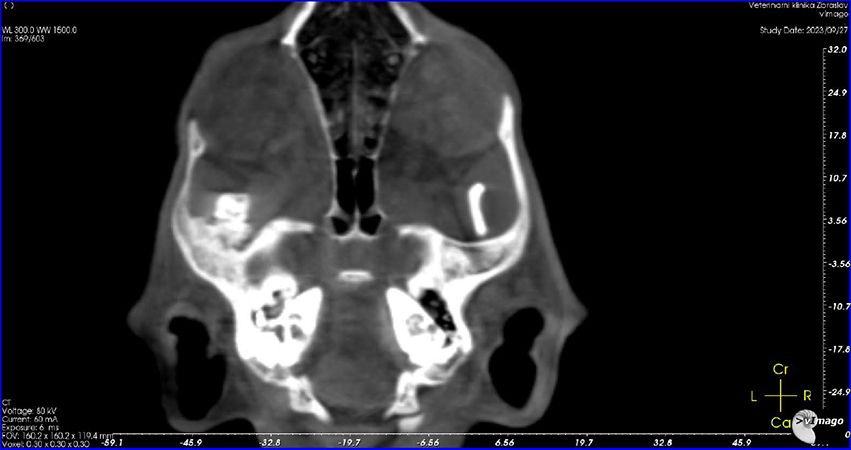

Leo absolvuje nové CT vyšetření. Je zřejmé, že oproti původní diagnóze (špatně zhojené poškození měkkých tkání), je z nových snímků jasně patrné, že Leo má špatně zhojenou zlomeninu spojení spodní čelisti a podočnicového oblouku na levé straně, což je důvod, proč se mu pusinka opět zavřela. Je nutná operace. Po krátké konzultaci v Nuslích Linda domlouvá, aby Lea odoperovali akutně na Zbraslavi. Dostává zprávu, 3D model i CT snímky do mailu.